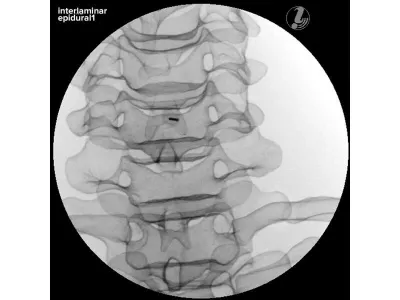

Тренажер для спинальной анестезии

Тренажер для спинальной анестезии (или эпидуральной анестезии) используется для обучения и тренировки медицинских специалистов, таких как анестезиологи и акушеры-гинекологи, в проведении данных процедур.

- Тренажер медицинский для анестезиологии и реаниматологии представляет собой модель нижней части торса человека, точно имитирующую анатомию поясничной области с костными ориентирами, позволяющую как измерять, так и забирать спинномозговую жидкость в реалистичных условиях

- В тренажере для отработки инъекций имеется анатомическая модель поясничного отдела позвоночника для более подробного изучения анатомии